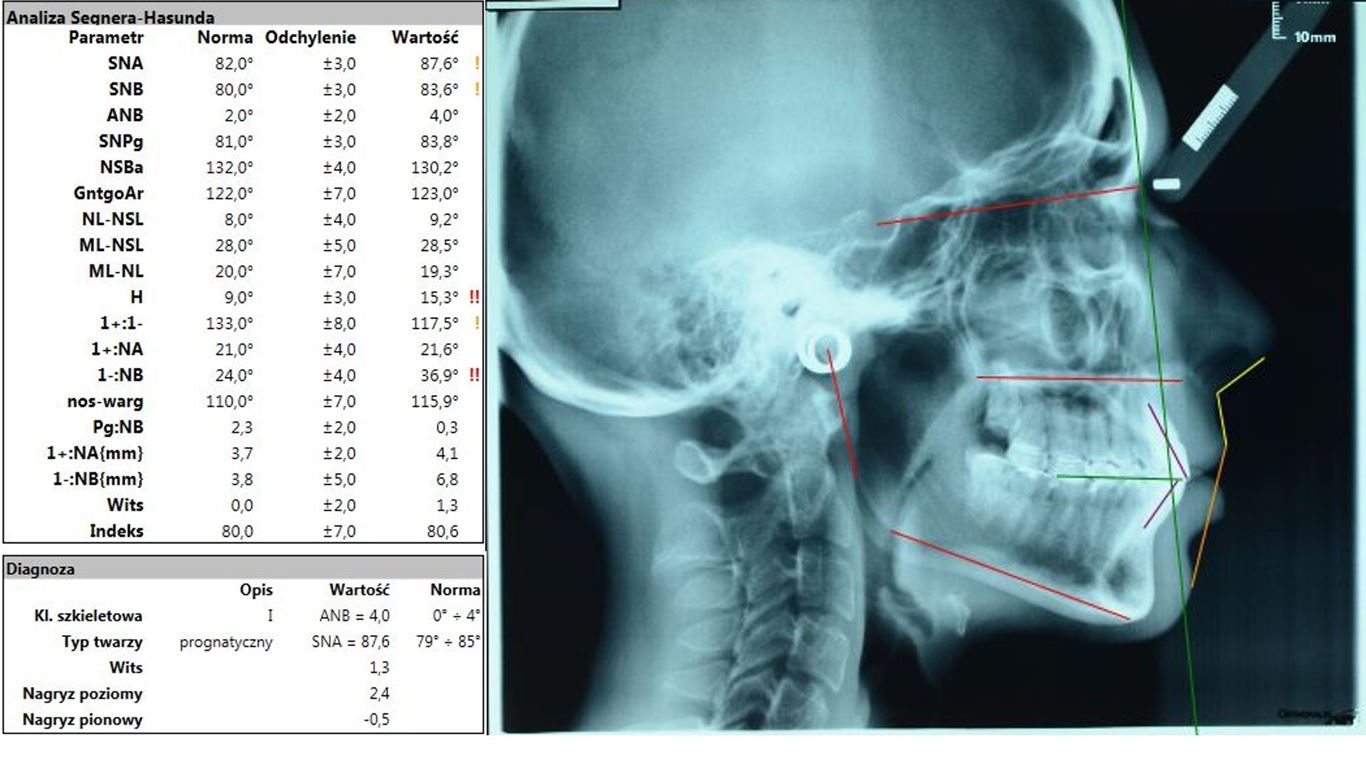

Minimalne zachodzenie pionowe, a w pozycji RC ustawienie zębów przednich w zgryzie tête à tête nasuwały podejrzenie wady gnatycznej. Analiza zdjęcia cefalometrycznego wykazała wprawdzie prognatyczny typ twarzy, jednak I klasę szkieletową, rotację i translację żuchwy w normie oraz neutralną relację sagitalną i wertykalną podstaw (ryc. 21). Pozwoliło to zaplanować poprawę relacji pomiędzy górnym i dolnym łukiem zębowym przez leczenie ortodontyczne poprzedzone ekstrakcją jednego dolnego zęba siecznego oraz dolnych zębów ósmych. Po leczeniu ortodontycznym zaplanowano chirurgiczne wydłużenie koron przednich zębów górnych i wykonanie adhezyjnych rekonstrukcji ceramicznych na wszystkich zębach szczęki i żuchwy z wyłączeniem drugich zębów trzonowych.